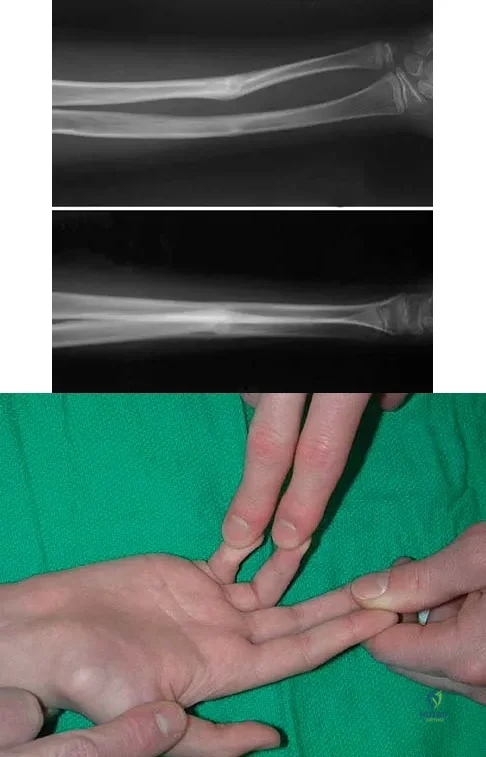

Figures 29a and 29b show the radiographs of a 13-year-old competitive gymnast who has had elbow pain for the past 2 weeks. The pain is worse with tumbling activities. Examination reveals a mild effusion and slight limitation of extension and forearm rotation with no locking. Initial management should consist of

Explanation

The radiographs show a lesion in the capitellum that is consistent with osteochondritis dissecans. There is no evidence of a loose body at this time. Initial management should consist of cessation of gymnastic activities. Nonsteroidal anti-inflammatory drugs and ice may help to alleviate acute symptoms; most symptoms usually resolve in 6 to 12 weeks. The patient may then begin range-of-motion and strengthening exercises, with a slow return to activities once full range of motion and good strength have been achieved. However, the prognosis for a return to high-level competitive gymnastics is guarded. Surgery is indicated for intra-articular loose bodies, a locked elbow, or failure of nonsurgical management. Surgery may be done either open or arthroscopically. Loose bodies should be removed, and cartilage flaps should be debrided. The results of bone grafting and internal fixation generally have been poor. Drilling the base of the defect may stimulate replacement with fibrocartilage, but the benefits of this procedure are not well documented. Maffulli N, Chan D, Aldridge MJ: Derangement of the articular surfaces of the elbow in young gymnasts. J Pediatr Orthop 1992;12:344-350. Bauer M, Jonsson K, Josefsson PO, Linden B: Osteochondritis dissecans of the elbow: A long-term follow-up study. Clin Orthop 1992;284:156-160.